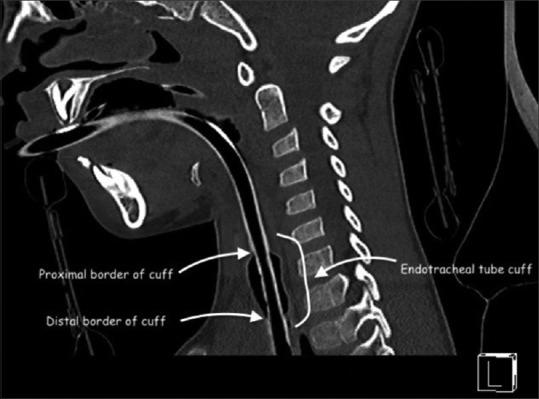

In this retrospective study, the ETT cuff position was examined on the sagittal plane images of neck and chest CT scans of 44 children. The position of the proximal and the distal aspect of the ETT cuff inside the trachea was recorded in relation to the vertebral levels. The vertebral levels were used to estimate the location of the cricoid ring and its relationship to the cuff.

The vertebrae were used as the primary landmarks to define the position of the cricoid and its relationship to the cuff of the ETT. Correlating vertebral levels with the cricoid for different age groups, the proximal (cephalad) edge of the ETT cuff was below the cricoid in 41 of 44 patients (93%). The ETT cuff was deep in 6 patients, below the 1 thoracic vertebra, with 2 ETTs in the right mainstem bronchus.

This is the first study demonstrating that the cuff of the ETT and its position in the trachea can be identified on CT imaging in children. The ETT cuff was below the level of the cricoid in the majority of patients irrespective of the patient's age as well as the size, make, and type of ETT.